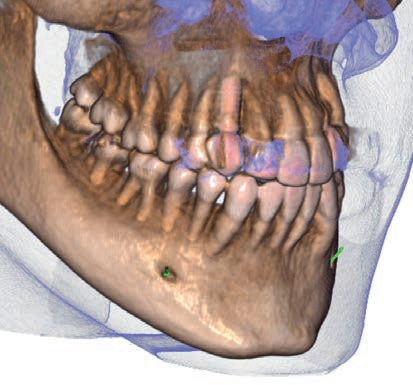

Hyperion X9 Pro 高端三合一全触摸摄影设备

HyperionX9pro是一台可以提供高品质二维及三维高分辨率图像,整合了先进技术的一站式、可升级、占地小巧的X射线摄影平台。它可以提供流畅的工作流程来满足各类诊断需求,为患者和操作者双方都能提供舒适的感受。

在SuperHD超高清模式下的高质量影像可以为医生的正确诊断提供有力的支撑。拍摄流程简单,系统也提供充分的操作指引。创新的设计带来方便的就位和友好的拍摄感受。